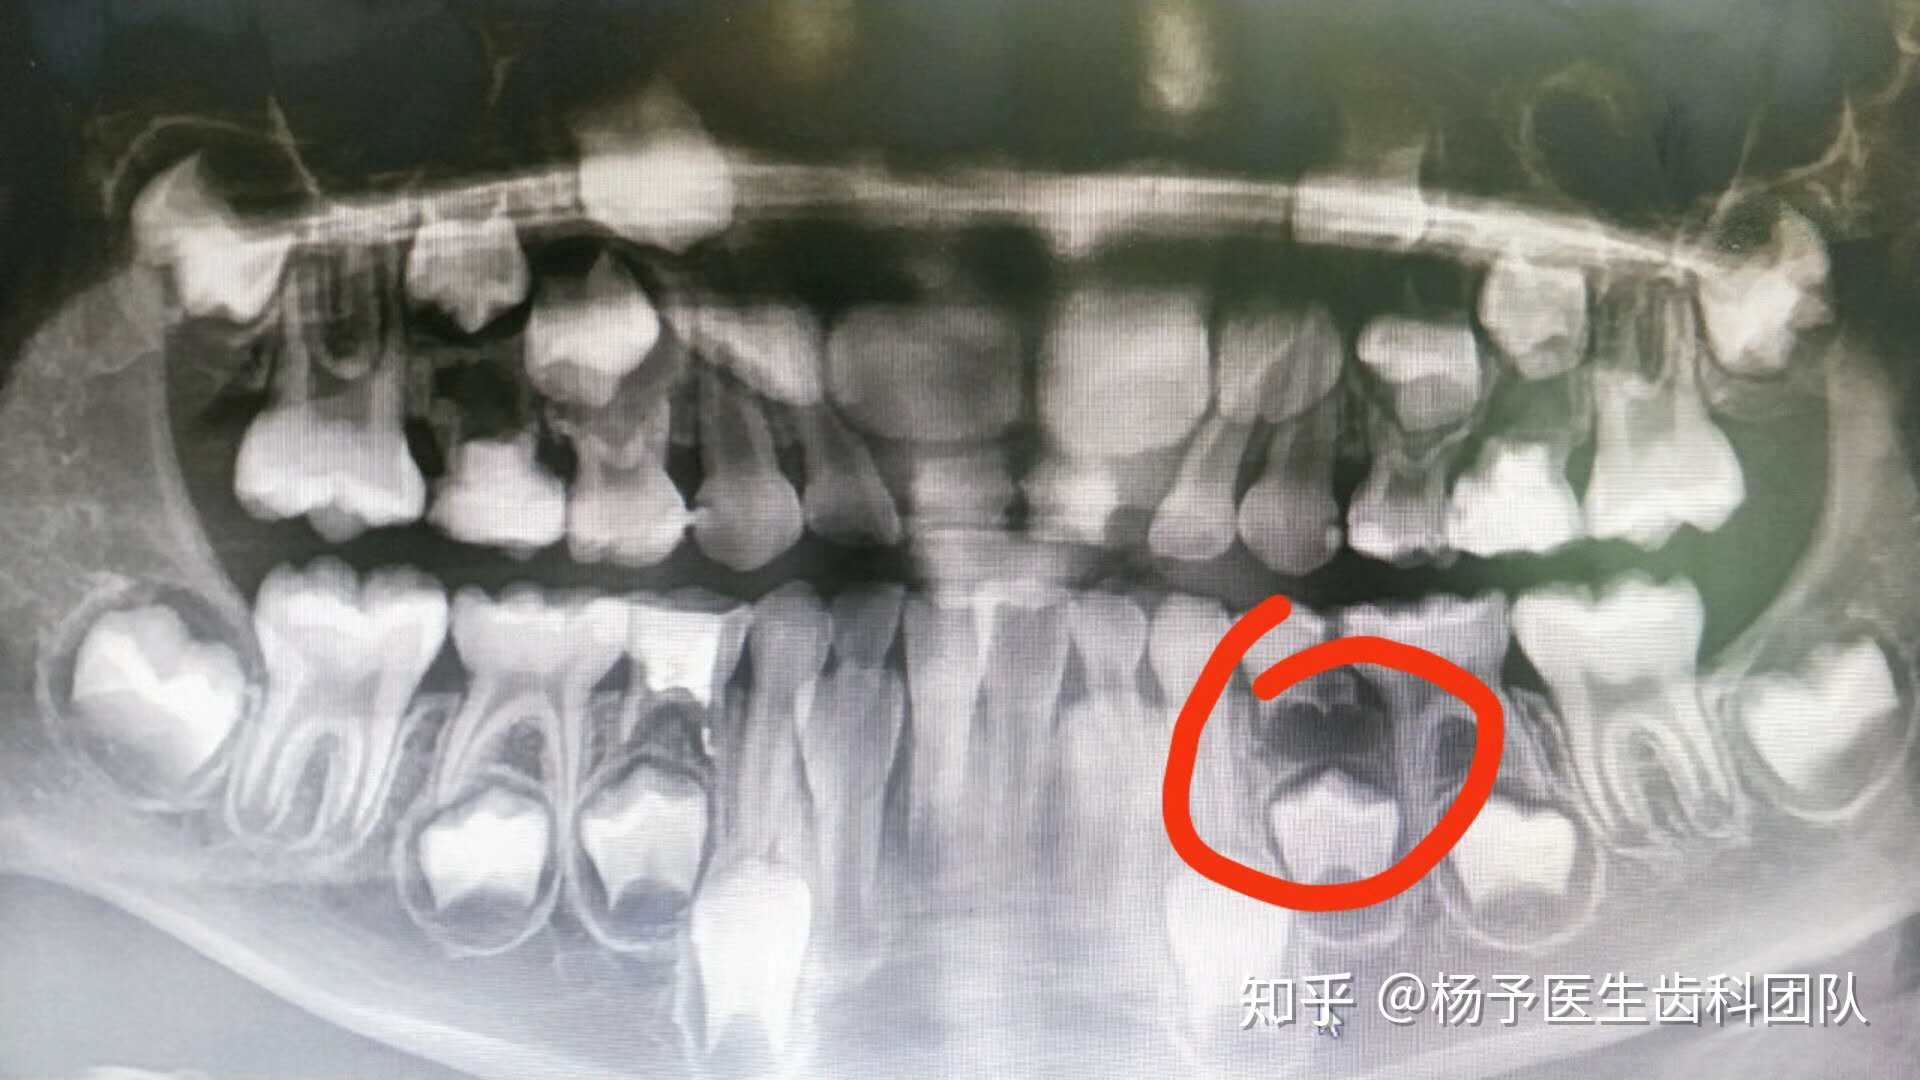

乳牙x光照,乳牙x光

这个'小病号',年仅5岁,由于乳牙的龋… - 知乎

没换牙的小孩的x光图

乳牙没掉恒牙长出图片